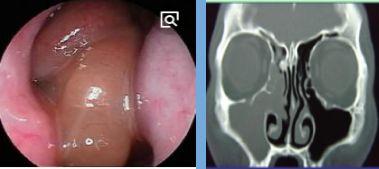

1、内镜检查:来源于中鼻道、嗅裂的黏脓性分泌物,中鼻道粘膜充血、水肿或有鼻息肉。

2、影像学检查:CT扫描显示窦口鼻道复合体或鼻窦粘膜病变。

• 鼻腔检查:前鼻镜、鼻内窥镜。

图1中鼻道息肉

图2 治疗后

正常鼻窦CT